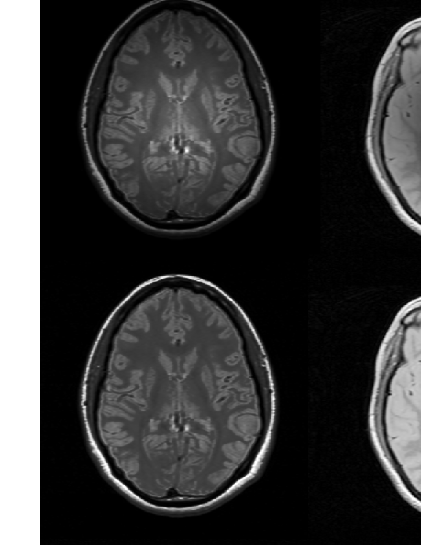

These operations are carried out by using the 3DVIEWNIX software ([22]). Based on the experiments in ([17, 4, 19]), minimum and maximum percentile values are set to and , respectively. In the standard scale, and are set to and . Figure 3 shows the original, corrected, and standardized (after correction) of two PD and two T2-weighted slices taken from two different studies in the first, second and third rows, respectively. The gain in the similarity of resulting image intensities for similar tissue types obtained can be readily seen.

![]() |